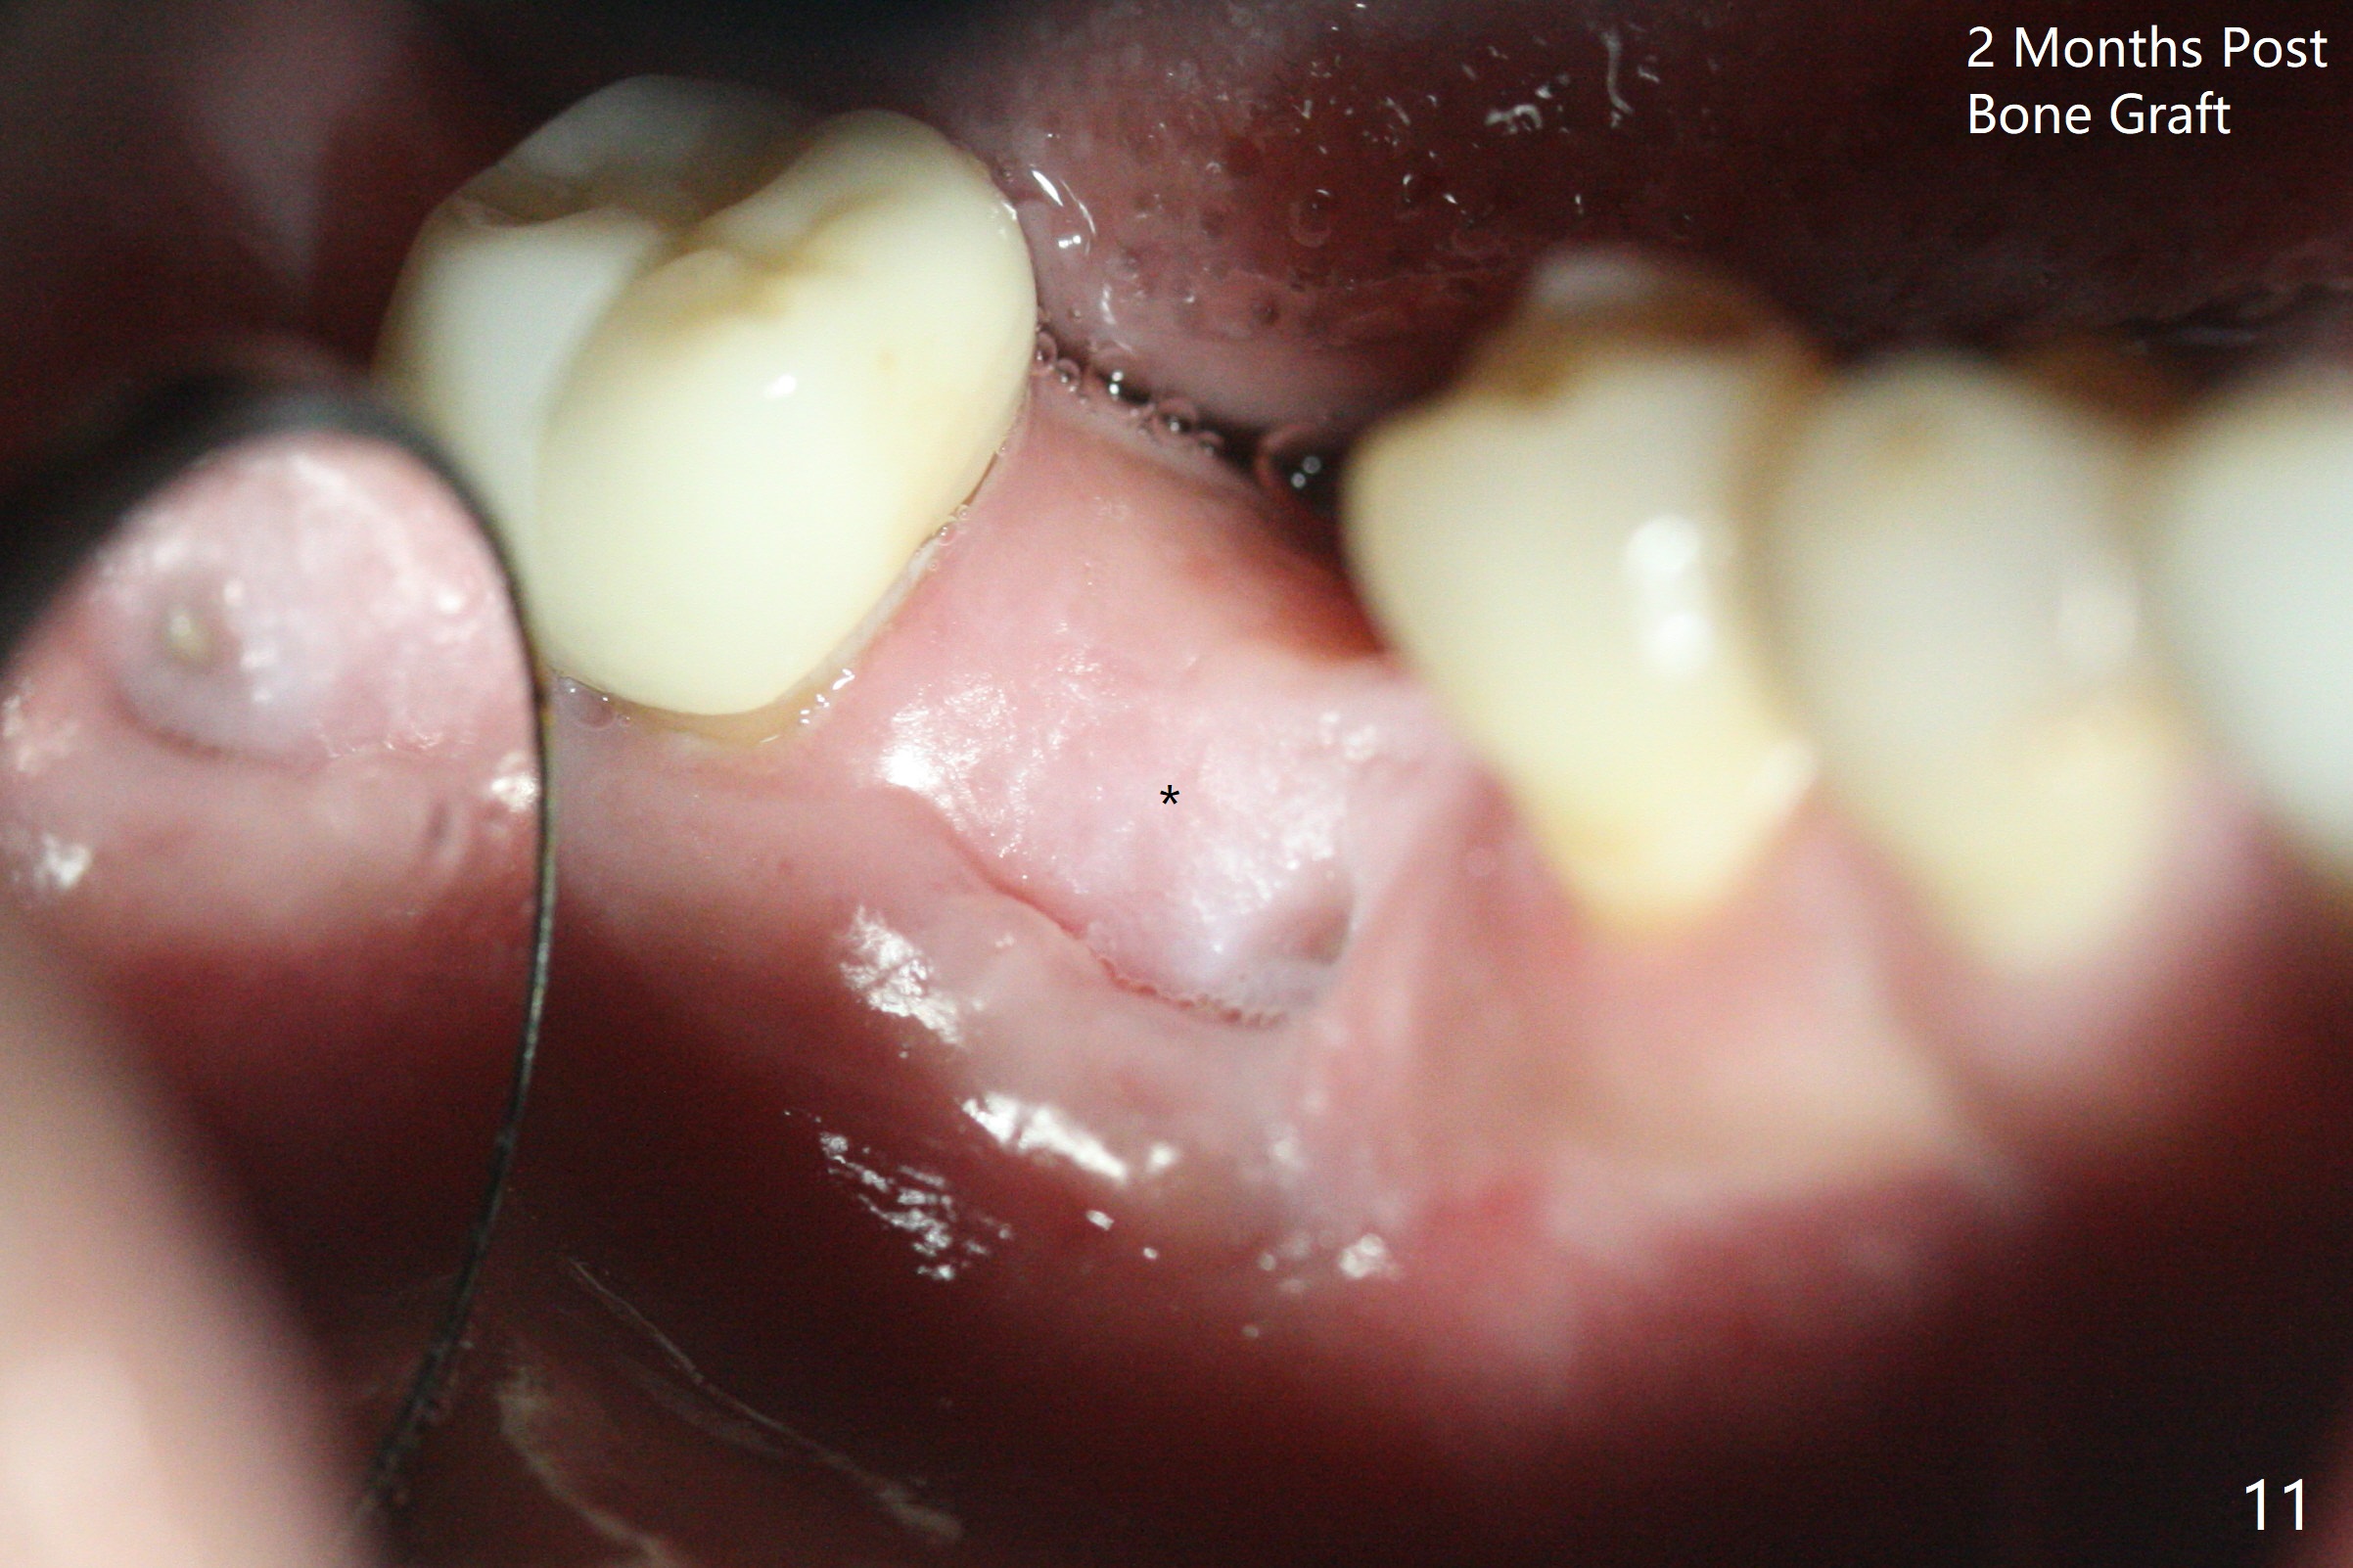

In spite of use of water pik, the coronal threads of the implant at #30 remain exposed 2 months postop (Fig.1). Envelop incision with mesial and distal accessory release ones reveals buccal bony defect (Fig.2). After 2nd spin (1500 RPM for 10 minutes), PRF forms in the red tube (Fig.3 yellow gel-like). Following use of Titanium brush, sticky bone is place (not so bone block-like, Fig.4), followed by a large piece of PRF membrane (from the red tube of Fig.3), Cytoplast (Fig.5,6 white porous) and a small piece of PRF membrane (from the white tube, next to the thin gingiva). The distal (Fig.6 D) and mesial (Fig.7 M) flaps are approximated (arrows without suture) as much as possible as well as lingual. 4-0 Polyglycolic Acid suture is used. Periodontal dressing dislodges 5 days postop. When the patient returns 1 week postop, he is pain free. Although Cytoplast is exposed, the surrounding gingiva seems to be healthy (Fig.8). Later the permanent crown of #31 is temporarily cemented with OHI. It appears that Cytoplast could be used to cover PRF membranes for soft tissue defect, followed by immediate provisional at the stage of immediate implant. The discolored (apparently contaminated) Cytoplast seems to be expelled 6 weeks postop (Fig.9). When the latter is removed, the soft tissue looks normal (Fig.10). Two weeks later, the apparently normal, but thin gingiva forms over the former granulation tissue (Fig.11 *, as compared to Fig.10). There is not enough bone coronal to the implant plateau 2 months post graft (Fig.12). Three months later, bone graft will be re-placed possibly with uncover.